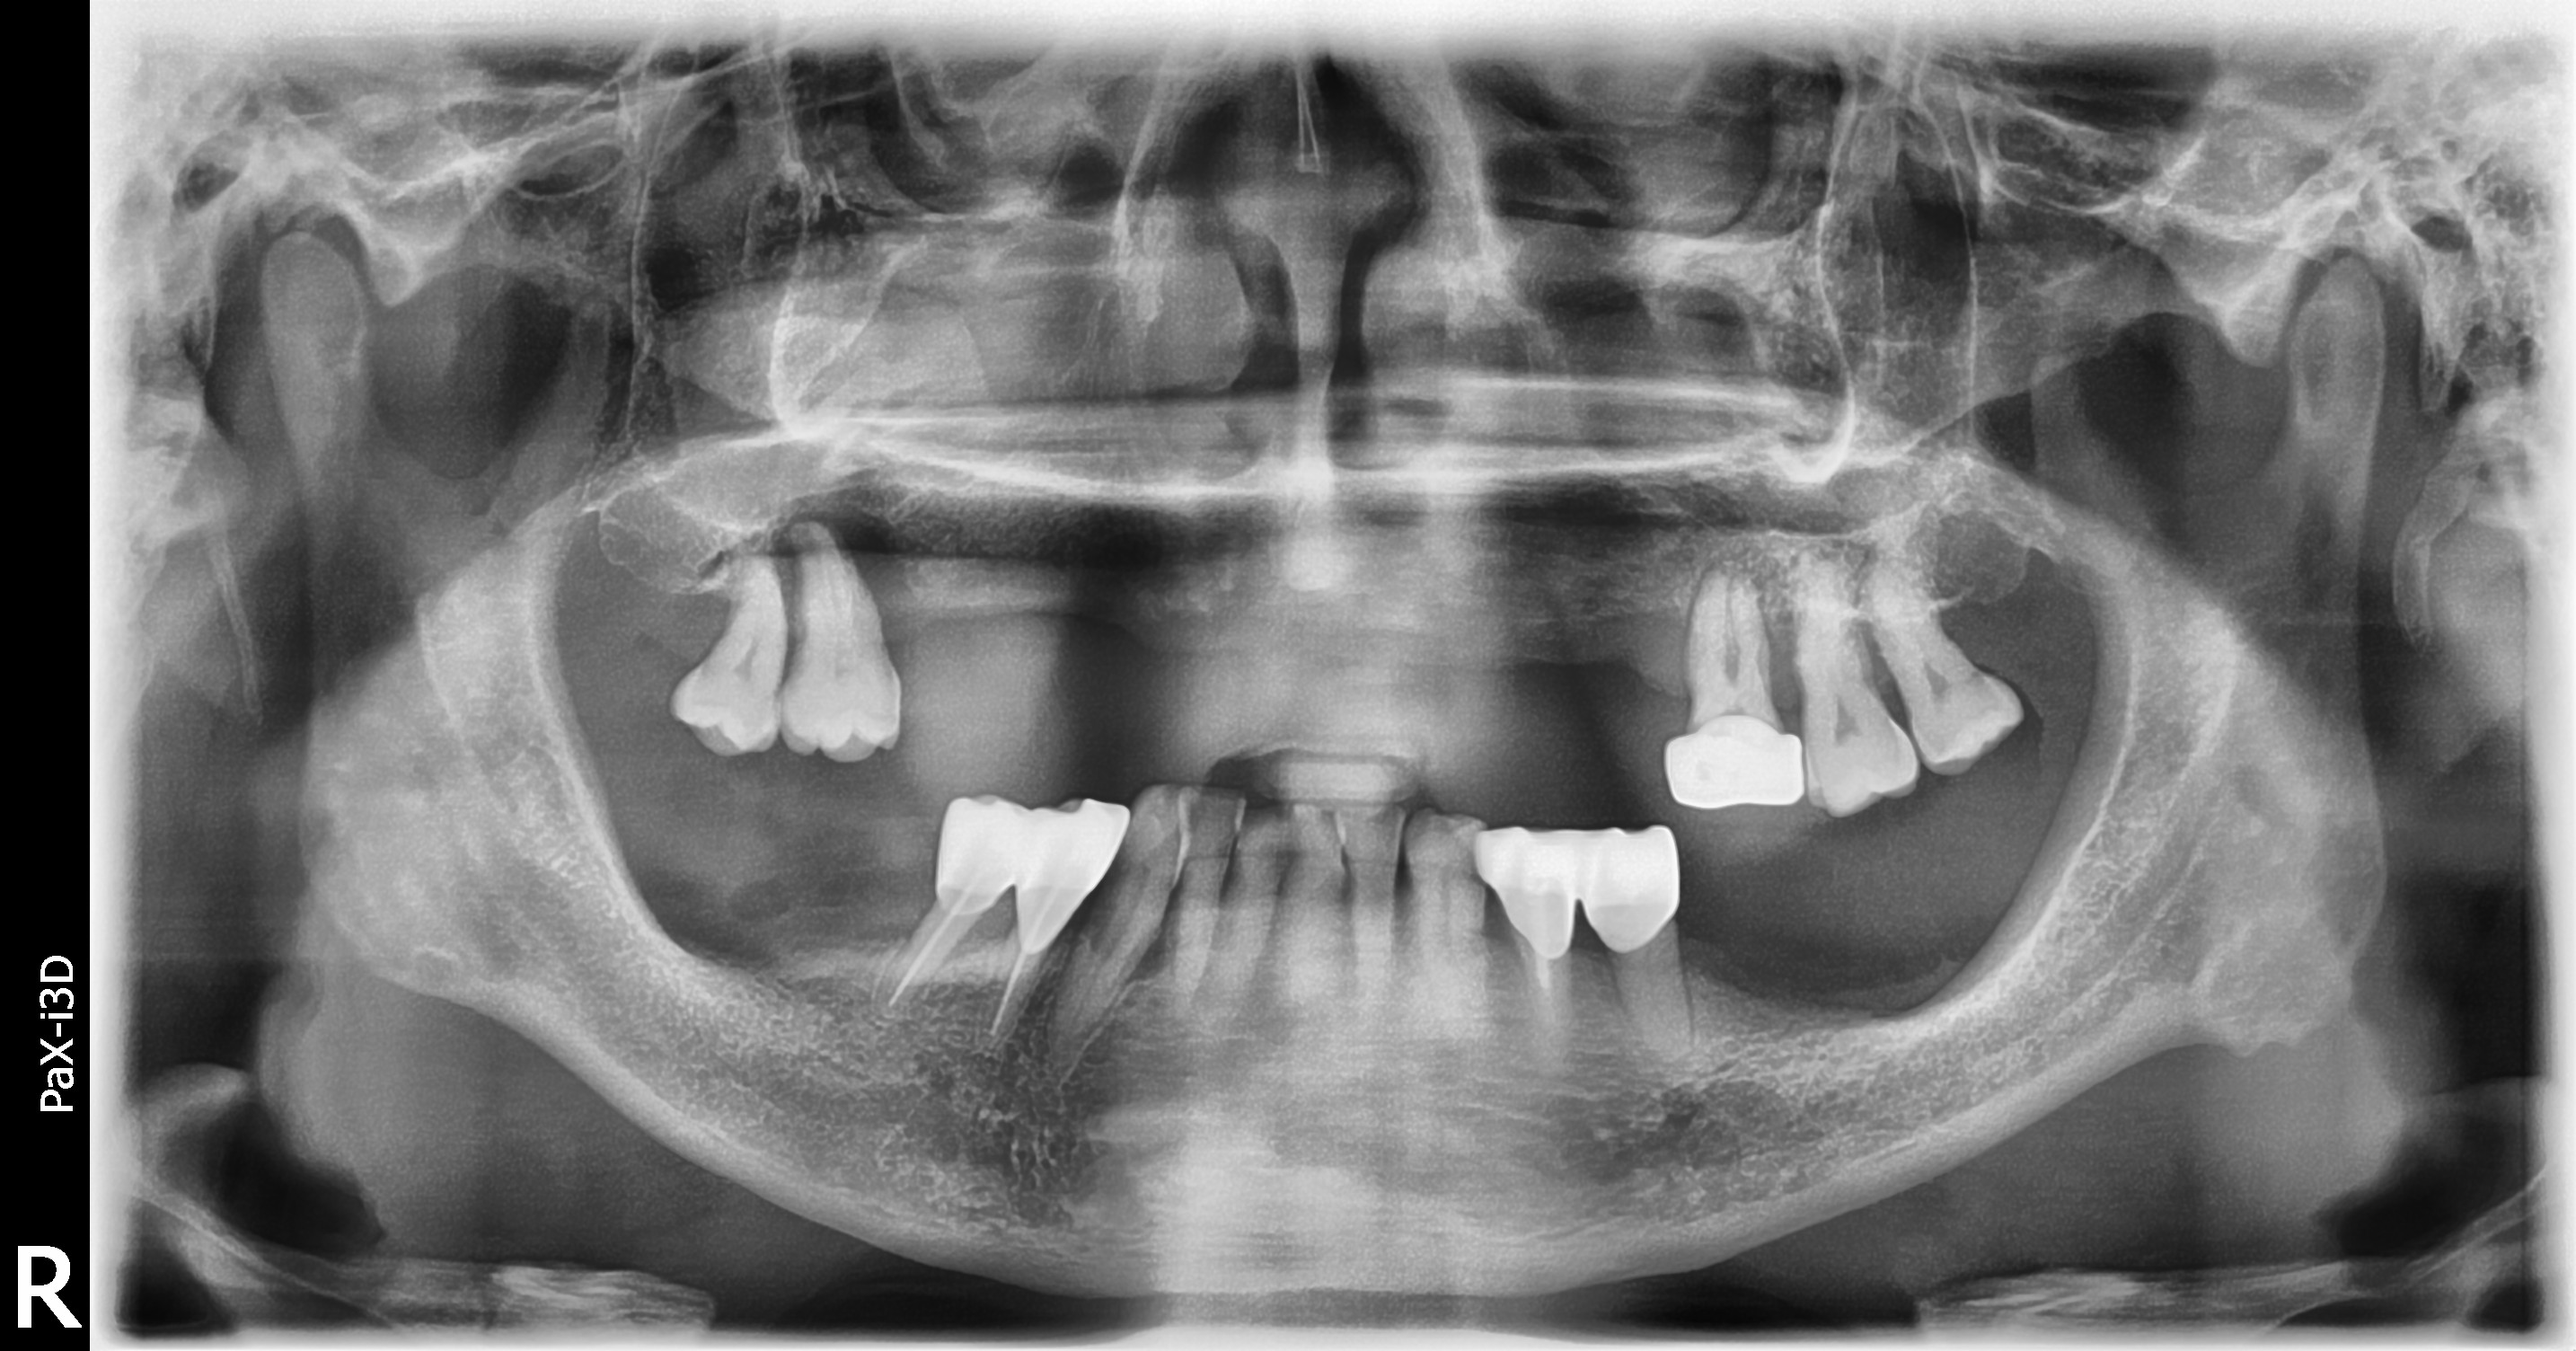

BEFOREAFTERBEFOREAFTER(식립)AFTER(착용)

임플란트 틀니

전체틀니